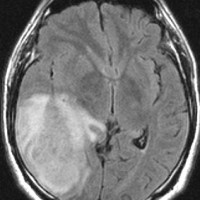

左がガドリニウム増強像で,手術ではこの部分が取れれば全摘出といわれるのですが,実際は右側のフレア画像で白っぽく見える所には腫瘍が滲み込んでいます。この部分を全て摘出してはじめて,画像上の全摘出といいます。全摘出は無理でしょう